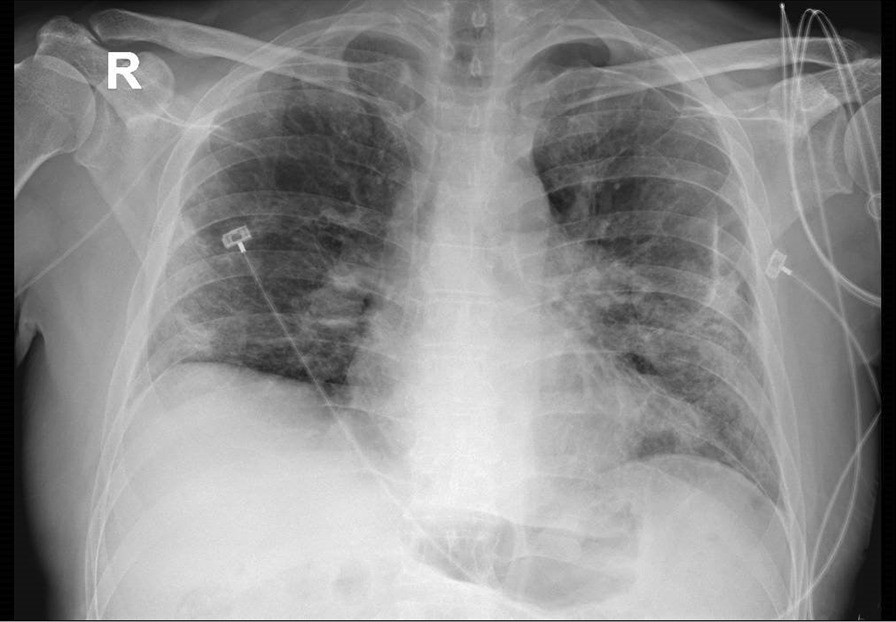

Laboratory investigation revealed an increase of high-sensitive troponin (90 ng/L, normal range < 54 ng/L), an elevated D-Dimer (3499 ng/ml), an increase of the white blood cell count (26,000), and a normal C-reactive protein (0.2 mg/L). Chest x-ray showed bilateral interstitial infiltrates with accentuation of the vascular plot, in the absence of pleural effusion (Fig. 1). Arterial blood gas at the time of the onset of dyspnea showed PH 7.38, PaCO2 22 mmHg, PaO2 48 mmHg, and bicarbonate 20 mmol/L. A reservoir 15 l/min was placed. On 70% FiO2, arterial blood gas showed PH 7.44, PaCO2 37.8 mmHg, PaO2 151 mmHg, and bicarbonate 16 mmol/L. An ECG showed a tachycardia, with a new onset right bundle branch block, S1, and Q3. At the transthoracic echocardiography, right-sided chambers were severely dilated. Due to the sudden clinical deterioration, thrombolysis with tissue plasminogen activator (tPA) was immediately performed in the suspicion of recurrent PE. The patient had a rapid beneficial effect with restoration of stable hemodynamic parameters.

Fig. 1.

Chest X Ray showing bilateral interstitial infiltrates with accentuation of the vascular plot, in the absence of pleural effusion